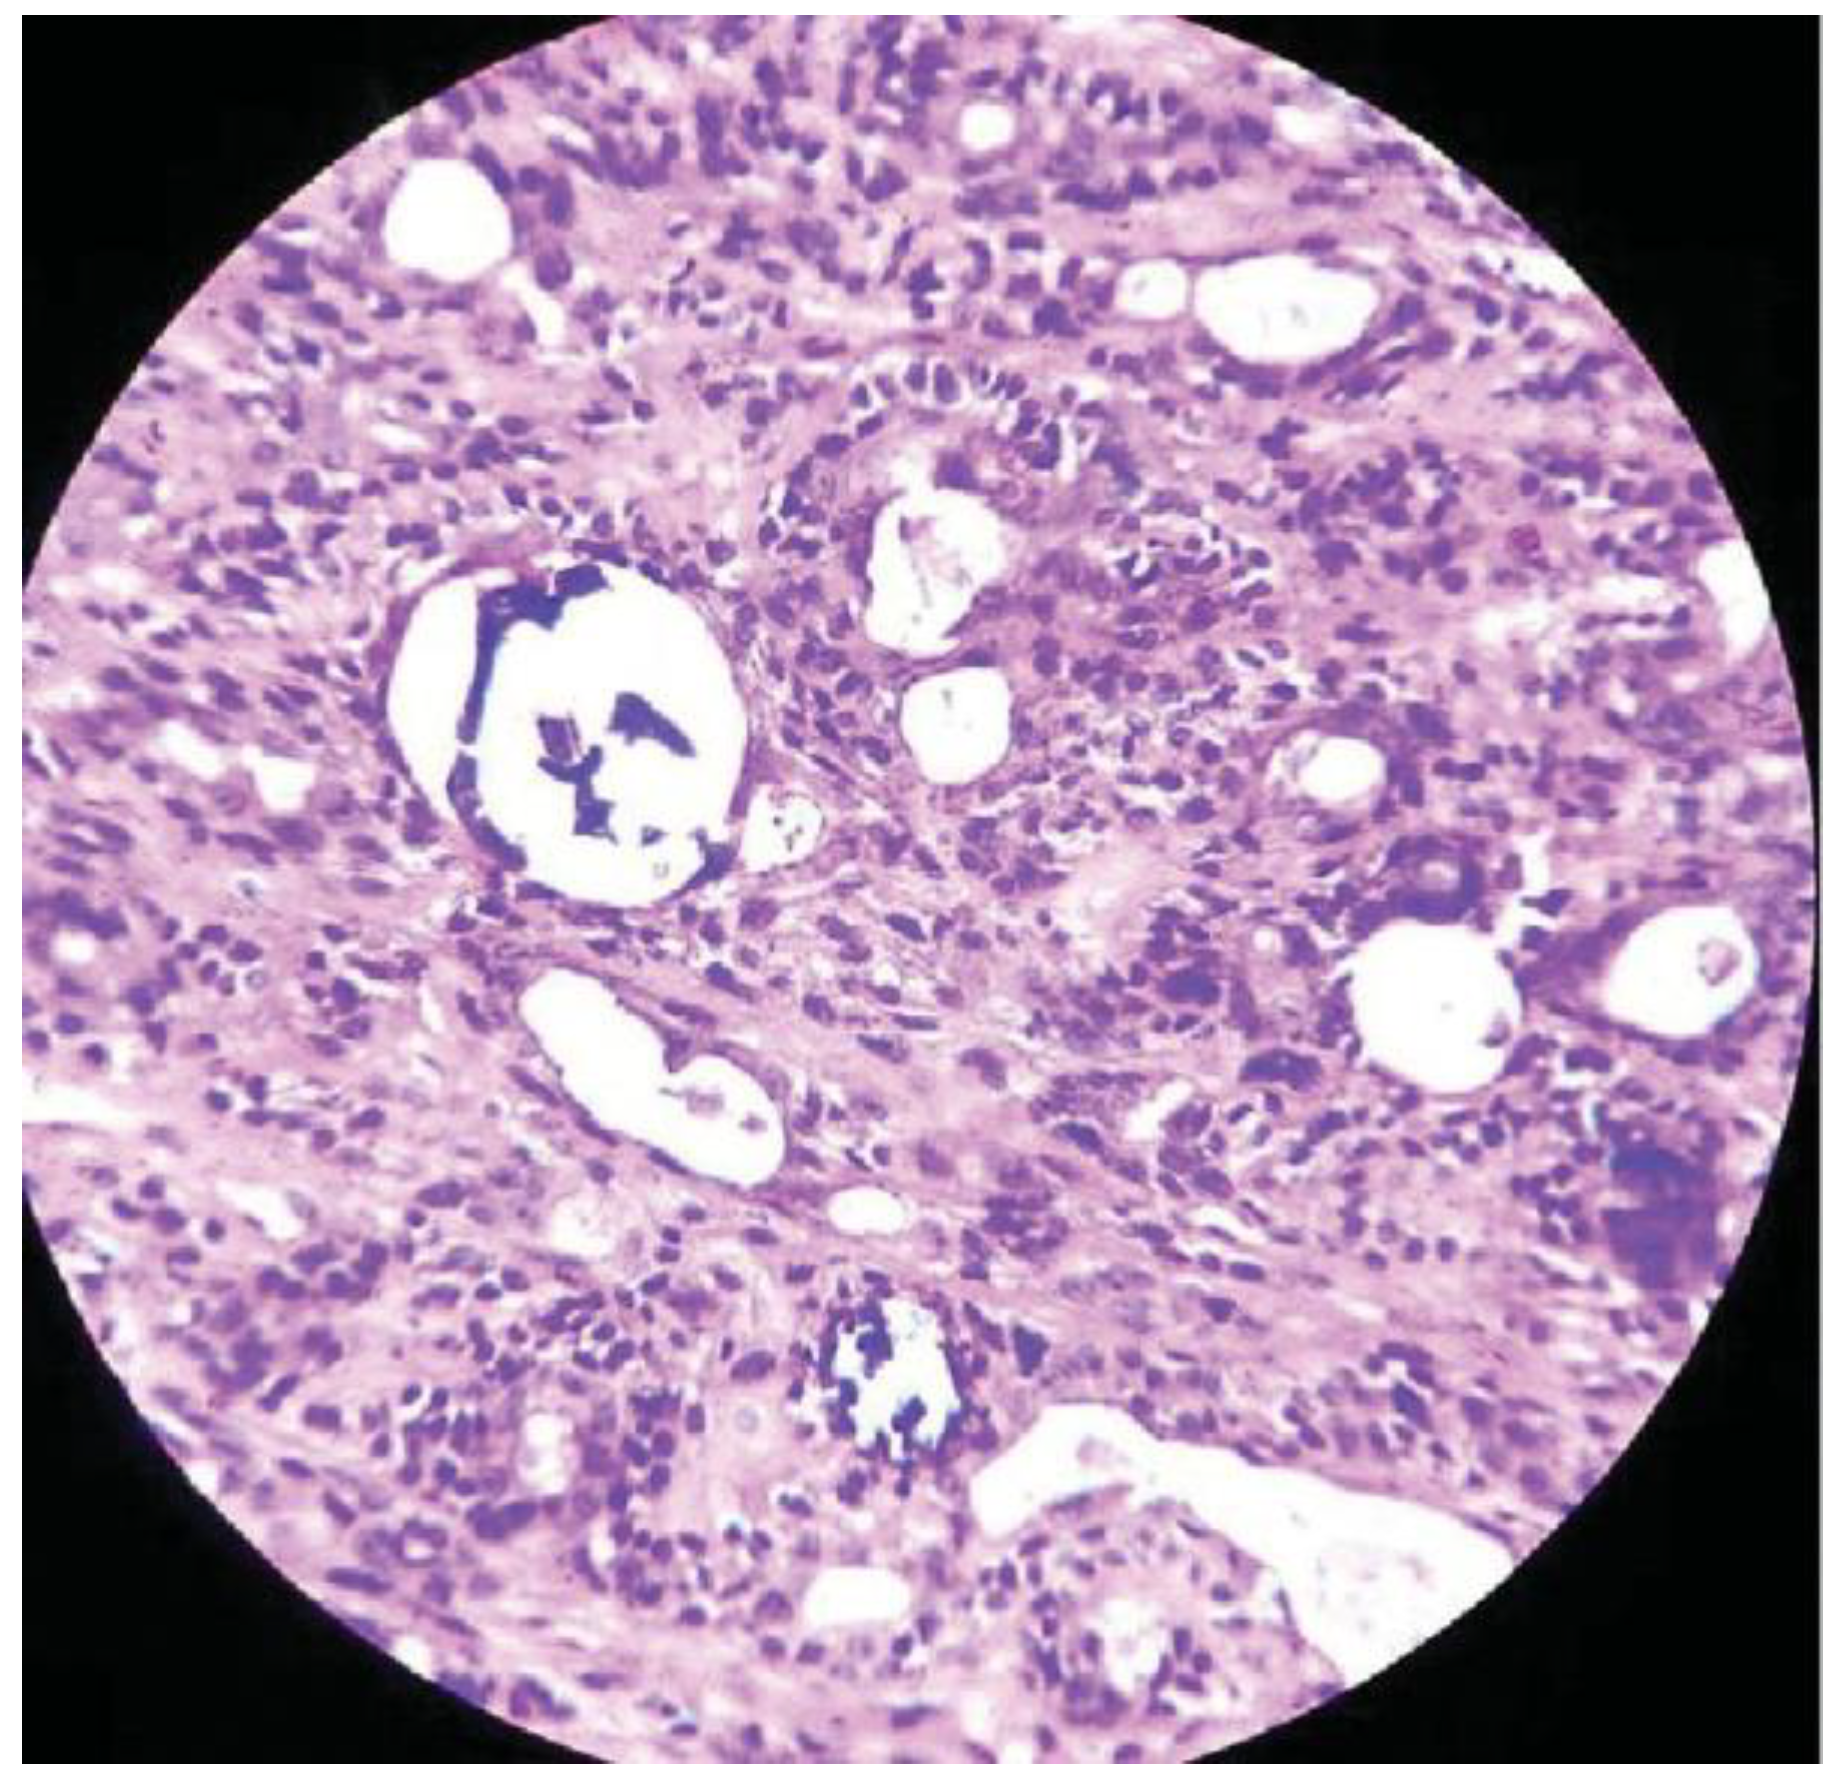

:Case Presentation

Discussion